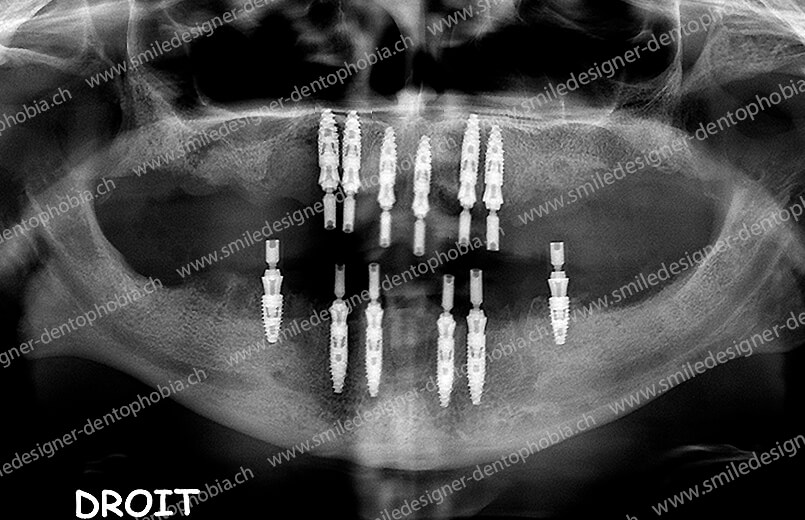

Cas clinique « DOMINO SURGERIES MCI » : Bridge implanto-porté sans extension postérieure (ALL ON 10/8). Version définitive des bridges avec un cosmétique en céramique. Double comblements de sinus et double greffes osseuses d’apposition pour la reconstruction du maxillaire.

Cas clinique « DOMINO SURGERIES MCI » : Bridge implanto-porté sans extension postérieure (ALL ON 8/6). Version définitive des bridges avec un cosmétique en céramique. Double comblements de sinus et double greffes osseuses d’apposition pour la reconstruction du maxillaire.

Cas clinique « DOMINO SURGERIES MCI » : Bridge implanto-porté avec extensions postérieures (ALL ON 6/6).

Version intermédiaire des bridges de première intention de Mise en Charge Immédiate (MCI) pour une resocialisation immédiate de la patiente cas en cours de cicatrisation des sinus lift et en attente des futurs implants postérieurs maxillaires.

Version définitive des bridges avec un cosmétique en céramique (ALL ON 10/6). Double comblements de sinus et double greffes osseuses d’apposition pour la reconstruction du maxillaire.